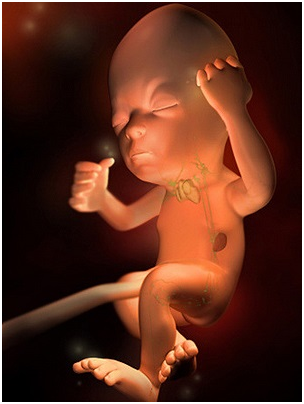

怀孕第9周胎儿图 B超图 三维图 那么,现在恭喜作为准妈妈的你,因为从现在开始,胚胎可...

怀孕第9周胎儿图 B超图 三维图 那么,现在恭喜作为准妈妈的你,因为从现在开始,胚胎可... -

怀孕第7周胚胎图 B超图 三维图 现在的胎儿还处于不稳定时期,像桑葚那么大,看起来还有...

怀孕第7周胚胎图 B超图 三维图 现在的胎儿还处于不稳定时期,像桑葚那么大,看起来还有... -

怀孕第7周现在的胎儿还处于不稳定时期,像桑葚那么大,看起来还有一个小尾巴。作为准妈妈的你,...

怀孕第7周现在的胎儿还处于不稳定时期,像桑葚那么大,看起来还有一个小尾巴。作为准妈妈的你,... -